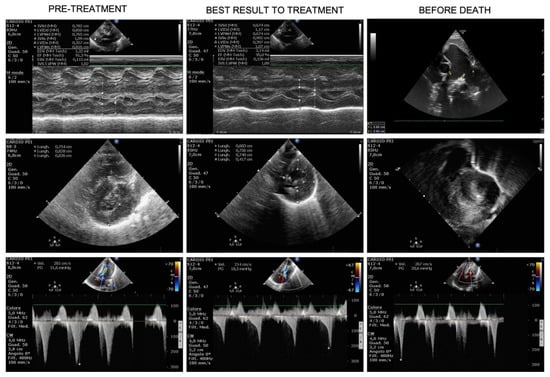

Figure 2.

Evolution over time of hypertrophic cardiomyopathy (HCM). Pre-treatment US (first column) shows severe HCM at M-mode Left Ventricle (Mm-LV, first row), short-axis LV (second row) and LV outflow track obstruction (CW-Doppler, third row), few days before treatment start. The best result under treatment is shown in the middle column: Mm-LV in first row, short-axis LV (second row) and LV outflow track obstruction (third row) demonstrated a consistent reduction of LV thickness and improvement of LV outflow track obstruction. The third column shows cardiac US three days before death: pulmonary artery dilatation is evident in the first row (2D), the rapid worsening of HCM, both in terms of LV thickness and obstruction are depicted in the last 2 rows (short-axis LV and CW-Doppler, respectively).

At day +46, a ventriculoperitoneal shunt was placed in order to manage the intraventricular hemorrhage and a red blood cell unit was transfused. After surgery, we observed rapid worsening of CHF (nt-pro-BNP increased from 2049 pg/mL to 47,000 pg/mL) as well as respiratory deterioration, requiring again mechanical ventilator support. Pulmonary artery dilation, stable until then, increased to 18 mm (+5.7 SDS) and death from untreatable CHF with hypoxic respiratory failure occurred on day +57. Figure 1 recapitulates the time course with septal thickness changes, left ventricular outflow (LVO) gradient and nt-pro-BNP changes across treatment. Figure 2 shows the ultrasound HCM evolution over time.

After treatment initiation there was a prompt improvement in clinical conditions (ROSS score from IV to III), allowing progressive and rapid withdrawal of inotropes in the next 4 days and weaning from mechanical ventilation a week later. Consistent with HCM stabilization, nt-pro-BNP decreased from 30,805 to 2355 pg/mL, and the patient was placed in non-invasive ventilator support and restricted fluid intake, with furosemide administration “as needed”. During the next month, treatment with Trametinib was continued without relevant side effects. ROSS score was II at 1 month. Liver enzymes, complete blood count, clotting tests, electrolytes, renal function were regularly monitored with no substantial modifications from baseline nor effects attributable to Trametinib administration. Echocardiography showed a tendency to HCM improvement with reduction of the septal thickness from treatment start to day +23. We also noted sudden dilation of the pulmonary artery dilation (14 mm, +3.5 SDS) at day 23. Despite of this finding, clinical conditions were stable in the following days and non-invasive ventilatory support was progressively reduced in terms of oxygen flow and fraction.